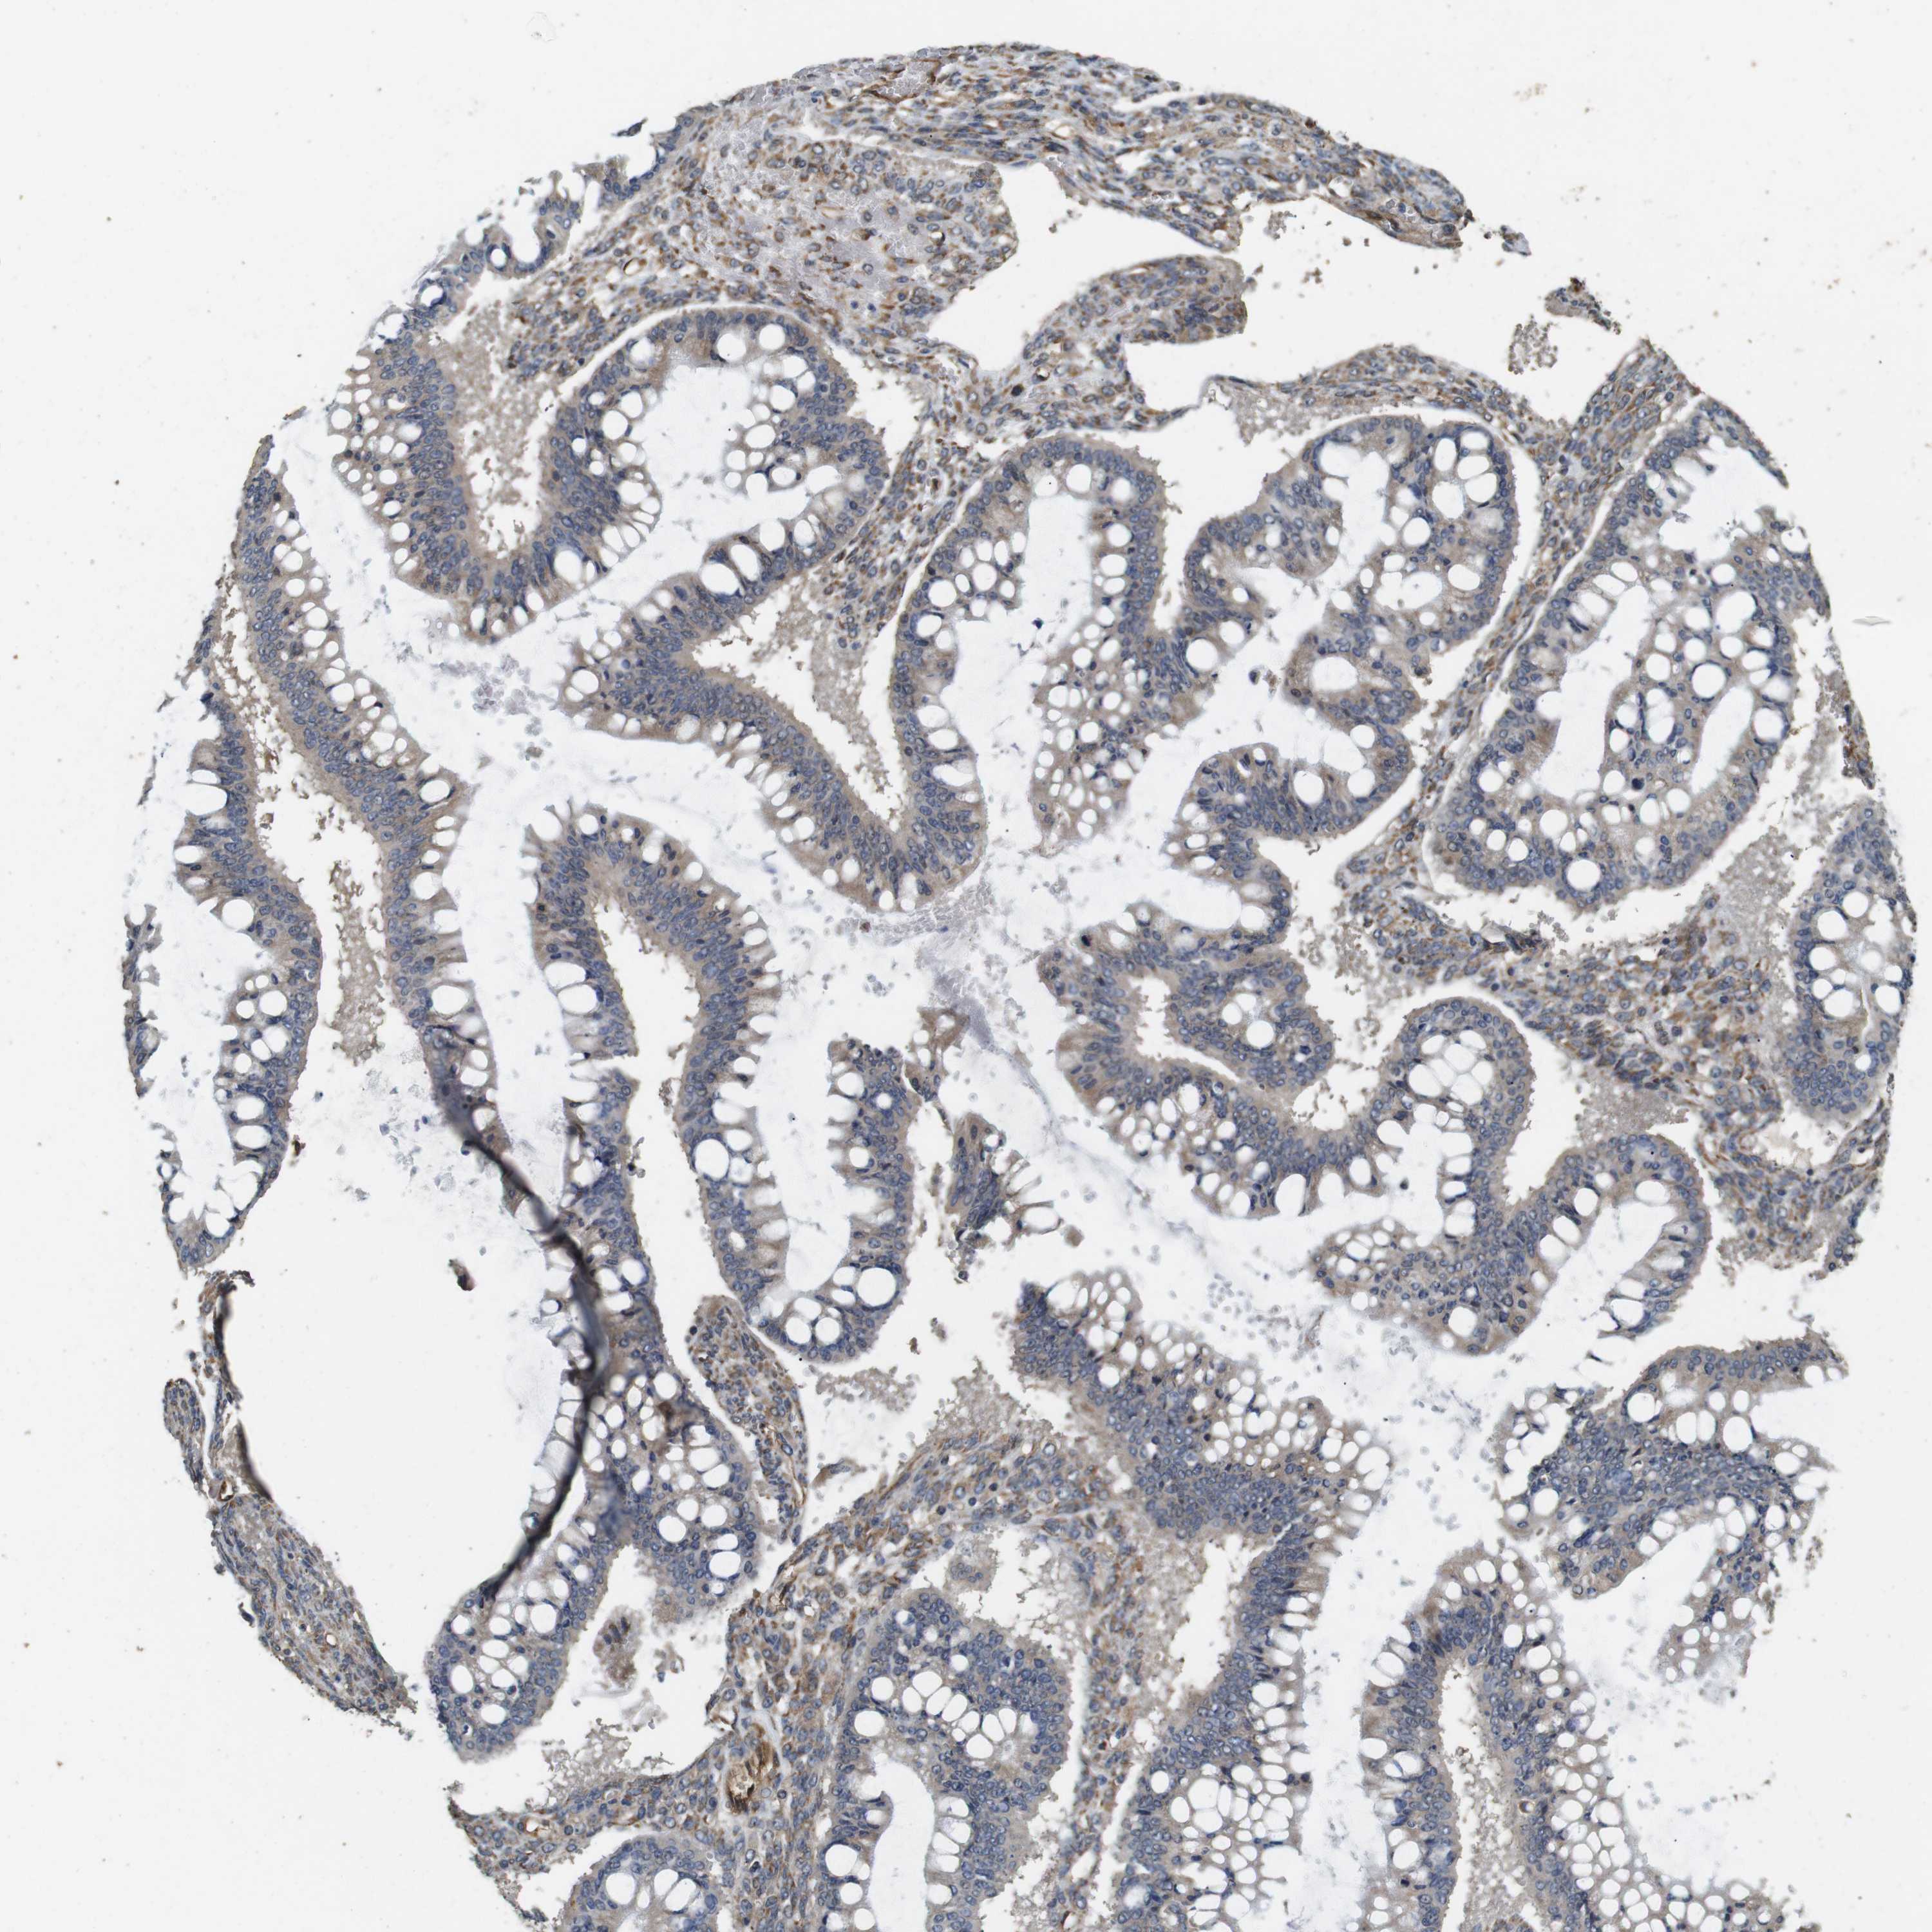

OVARIAN CANCER - Protein expressioni

A mouse-over function shows sample information and annotation data. Click on an image to view it in a full screen mode. Samples can be filtered based on level of antibody staining by selecting one or several of the following categories: high, medium, low and not detected. The assay and annotation is described here.

Note that samples used for immunohistochemistry by the Human Protein Atlas do not correspond to samples in the TCGA dataset.

Antibody stainingi

Antibody staining in the annotated cell types in the current human tissue is reported as not detected, low, medium, or high, based on conventional immunohistochemistry profiling in selected tissues. This score is based on the combination of the staining intensity and fraction of stained cells.

Each image is clickable and will lead to virtual microscopy that enables deeper exploration of all samples and also displays staining intensity scores, fraction scores and subcellular localization as well as patient and tissue information for each sample.

Antibody HPA014166

Antibody HPA025240

Cystadenocarcinoma, serous, NOS

Carcinoma, endometroid

Cystadenocarcinoma, mucinous, NOS

Carcinoma, NOS